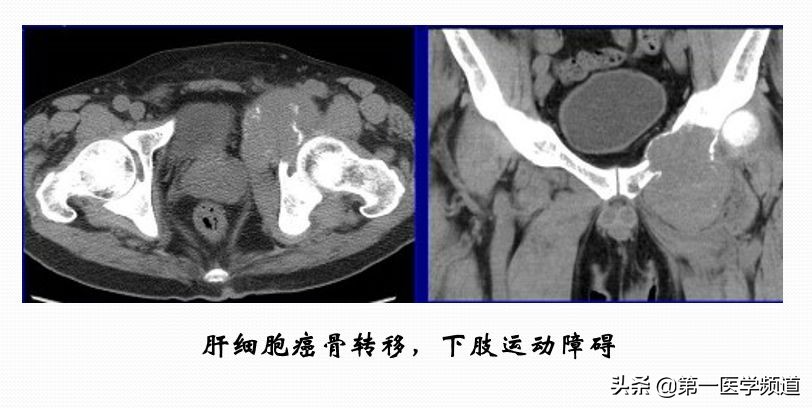

这是一个肝癌骨转移的病人。临床上病人骨质有明显的破坏,造成了下肢行动障碍,疼痛非常显著。做了完全性的冷冻消融,整个肿瘤凝固性坏死。临床上,对病人来说,疼痛的缓解非常明显,术后18个月坏死组织明显地缩小,也未见肿瘤的复发,肿瘤病灶完全坏死。